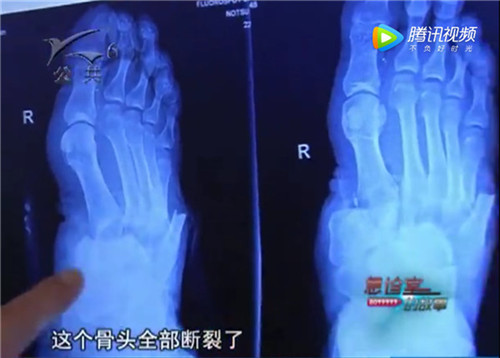

急诊室医生详细检查后发现,黄师傅右脚掌从中间断裂,只有少许皮肤粘连,在伤口的创面处,已经有细菌感染的迹象,伤势非常严重,需要及时处理,不然这只脚很有可能就要完全截肢。

脚伤非常严重,要是保不住对黄师傅以及他的家庭影响都非常大,为了挽留他脚的功能,医生突然提出一个大胆的想法,在黄师傅身上“就地取材”再造出一个新的足面,术后尽量不影响他正常生活。于是全院专家紧急会诊,开始商讨再造足手术方案。